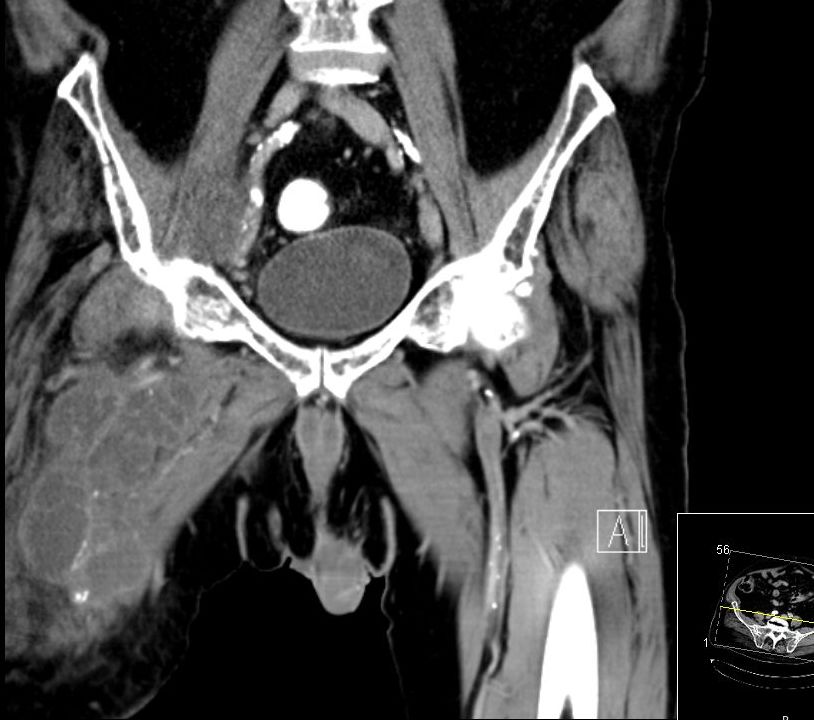

74-jähriger Mann, der vor 2 Jahren eine Beinamputation rechts wegen eines Chondrosarkoms der Tibia hatte. Jetzt ausgedehnte Knoten in der rechten Leiste. |